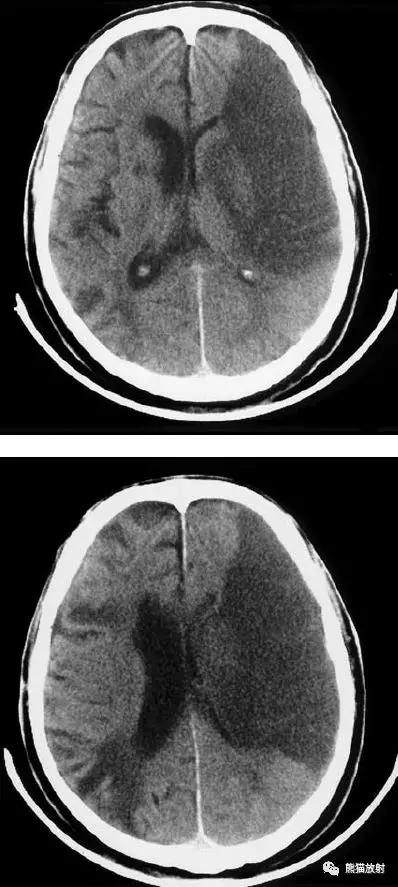

大脑中动脉区梗死:部分梗死,仅累及左侧浅表区域。

左侧大脑中动脉区完全梗死,对邻近的侧脑室产生占位效应;右侧可见其他较小的缺血性低密度区。

右侧大脑前动脉供血区部分梗死

右侧大脑后动脉供血区梗死

双侧大脑后动脉供血区梗死

右侧大脑前、中动脉供血区梗死,可见明显占位效应。

右侧大脑前、中、后动脉供血区巨大梗死